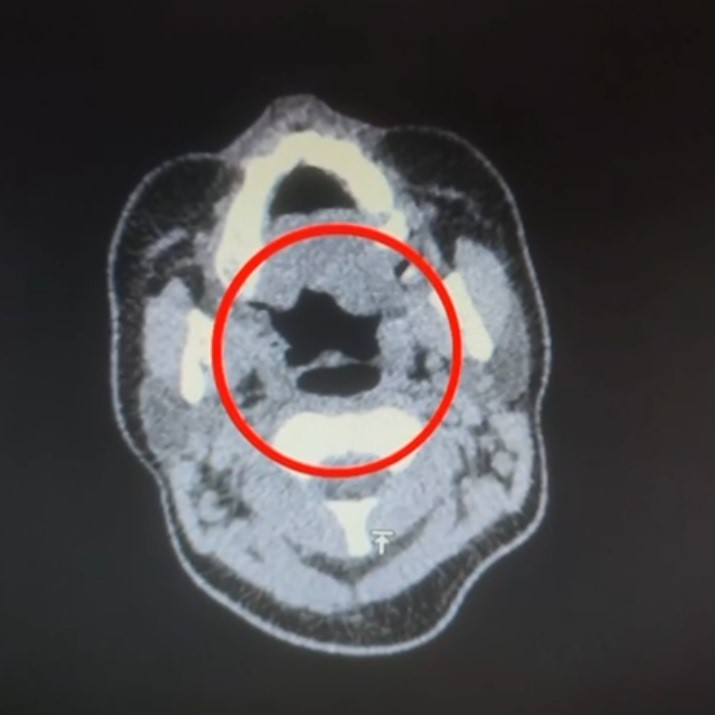

Operasyonda gözaltına alınan A.R. (27) hastaneye götürüldü. Yapılan iç beden muayenesinde, midesinde 50 adet kapsül halinde toplam 500 gram uyuşturucu madde tespit edildi.